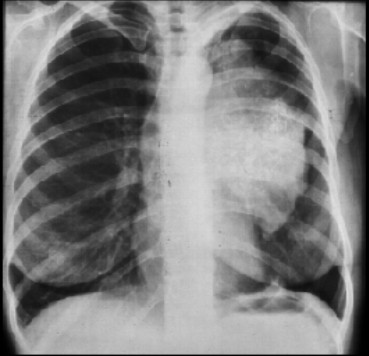

Ung thư phổi trái

Một số ít người bệnh ung thư phổi (khoảng 10%) không có triệu chứng, tình cờ chụp phim ngực (chest X-ray, chúng ta hay quen miệng gọi “phim phổi”) vì lý do nào khác, thấy khối ung thư. Còn đa số người bệnh có triệu chứng lúc ung thư được tìm ra.

Với những triệu chứng đáng ngờ kể trên, khiến chúng ta nghĩ đến ung thư phổi, bước đầu là chụp một phim ngực. Nếu phim ngực cho thấy quả có khối bướu, chúng ta cần làm nhiều thứ nữa để xác định giai đoạn tiến triển của ung thư; điều này rất quan trọng trong việc quyết định sẽ chữa trị bằng phương cách này.